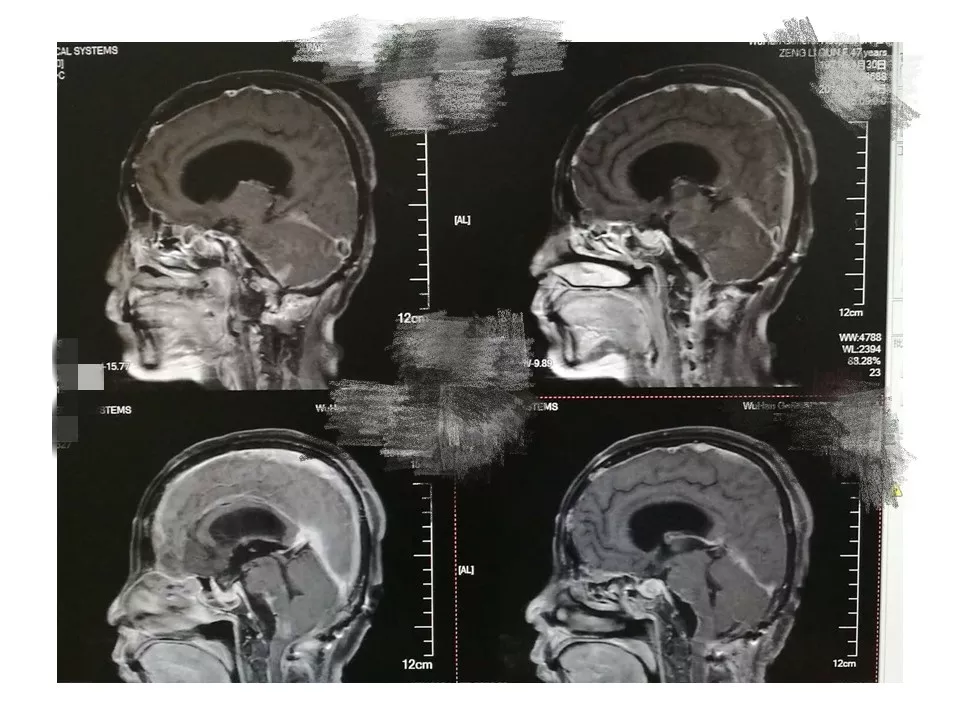

今天为大家分享的是《贝朗时间》第三十八期,由中国人民解放军武汉总医院神经外科副主任姚国杰教授带来的:远外侧入路全斜坡巨大脑膜瘤显微手术1例,欢迎阅读、分享!

远外侧入路全斜坡巨大脑膜瘤显微手术1例